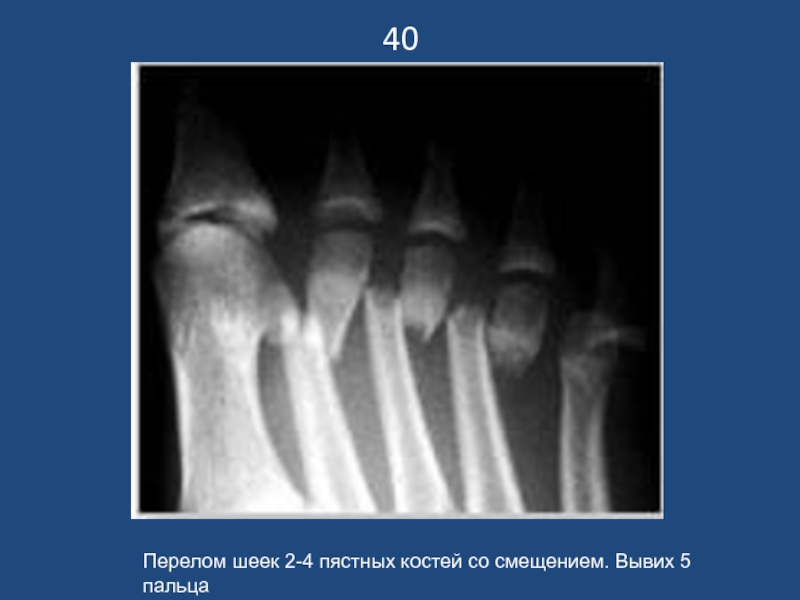

Перелом шеек 2-4 пястных костей со смещением. Вывих 5 пальца

40Перелом шеек 2-4 пястных костей со смещением. Вывих 5 пальца